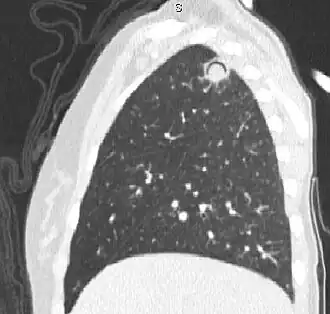

При рентгенографии и КТ-исследовании, аспергиллёз лёгких в классических случаях манифестирует «симптомом ореола» (перифокальным отёком и геморрагическим пропитыванием) вокруг округлого или треугольного фокуса уплотнения, в дальнейшем с формированием «симптома серпа» (отражающего некроз в толще воспалительного очага)[4]. У гематологических пациентов с инвазивным аспергиллёзом исследование галактоманнана позволяет поставить диагноз неинвазивным способом.